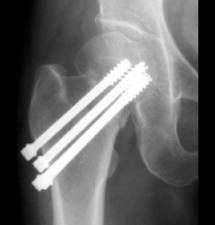

Для остеосинтеза переломов шейки бедренной кости применяют спонгиозные канюлированные винты диаметром 6,5 мм, конструкции DHS (dynamic hip screw), угловые 130 градусов пластины.

Спонгиозные канюлированные винты вводят по направляющим спицам из кондуктора, расположенного в подвертельной области бедра под контролем электронно-оптического преобразователя (ЭОП). Эта операция малотравматичная и подходит для больных в возрасте старше 60 лет.

Под контролем ЭОП проксимальный винт с шайбой проводится в верхний квадрант головки до субхондрального слоя. По сопротивлению руке при его введении можно косвенно судить о плотности кости. Следующие два винта проводятся в нижний квадрант ближе к дуге Адамса. Два-три шва на мышцы и фасцию. Дренирование раны если необходимо. Швы на кожу. Продолжительность операции 20-30 мин. Время рентген-экспозиции около 5-7 мин. Отказ от применения направляющих спиц, сверла и метчика (при остеопорозе) максимально упрощают операцию и сокращают ее время.